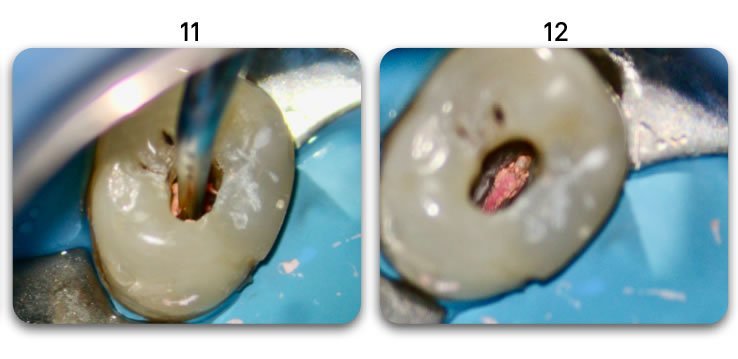

Template for x-rays

Biolight® DRILL-FREE posts are available in bundles of 4, 6, 9 and 12 strands. The post size is selected based on the width of the canal at the coronal area. Depending upon the canal width at the apical stop, a certain number of strands must be pushed to the stop. Both of the measurements are made with the assistance of a radiograph and the template that is included in the TRAINING KIT.